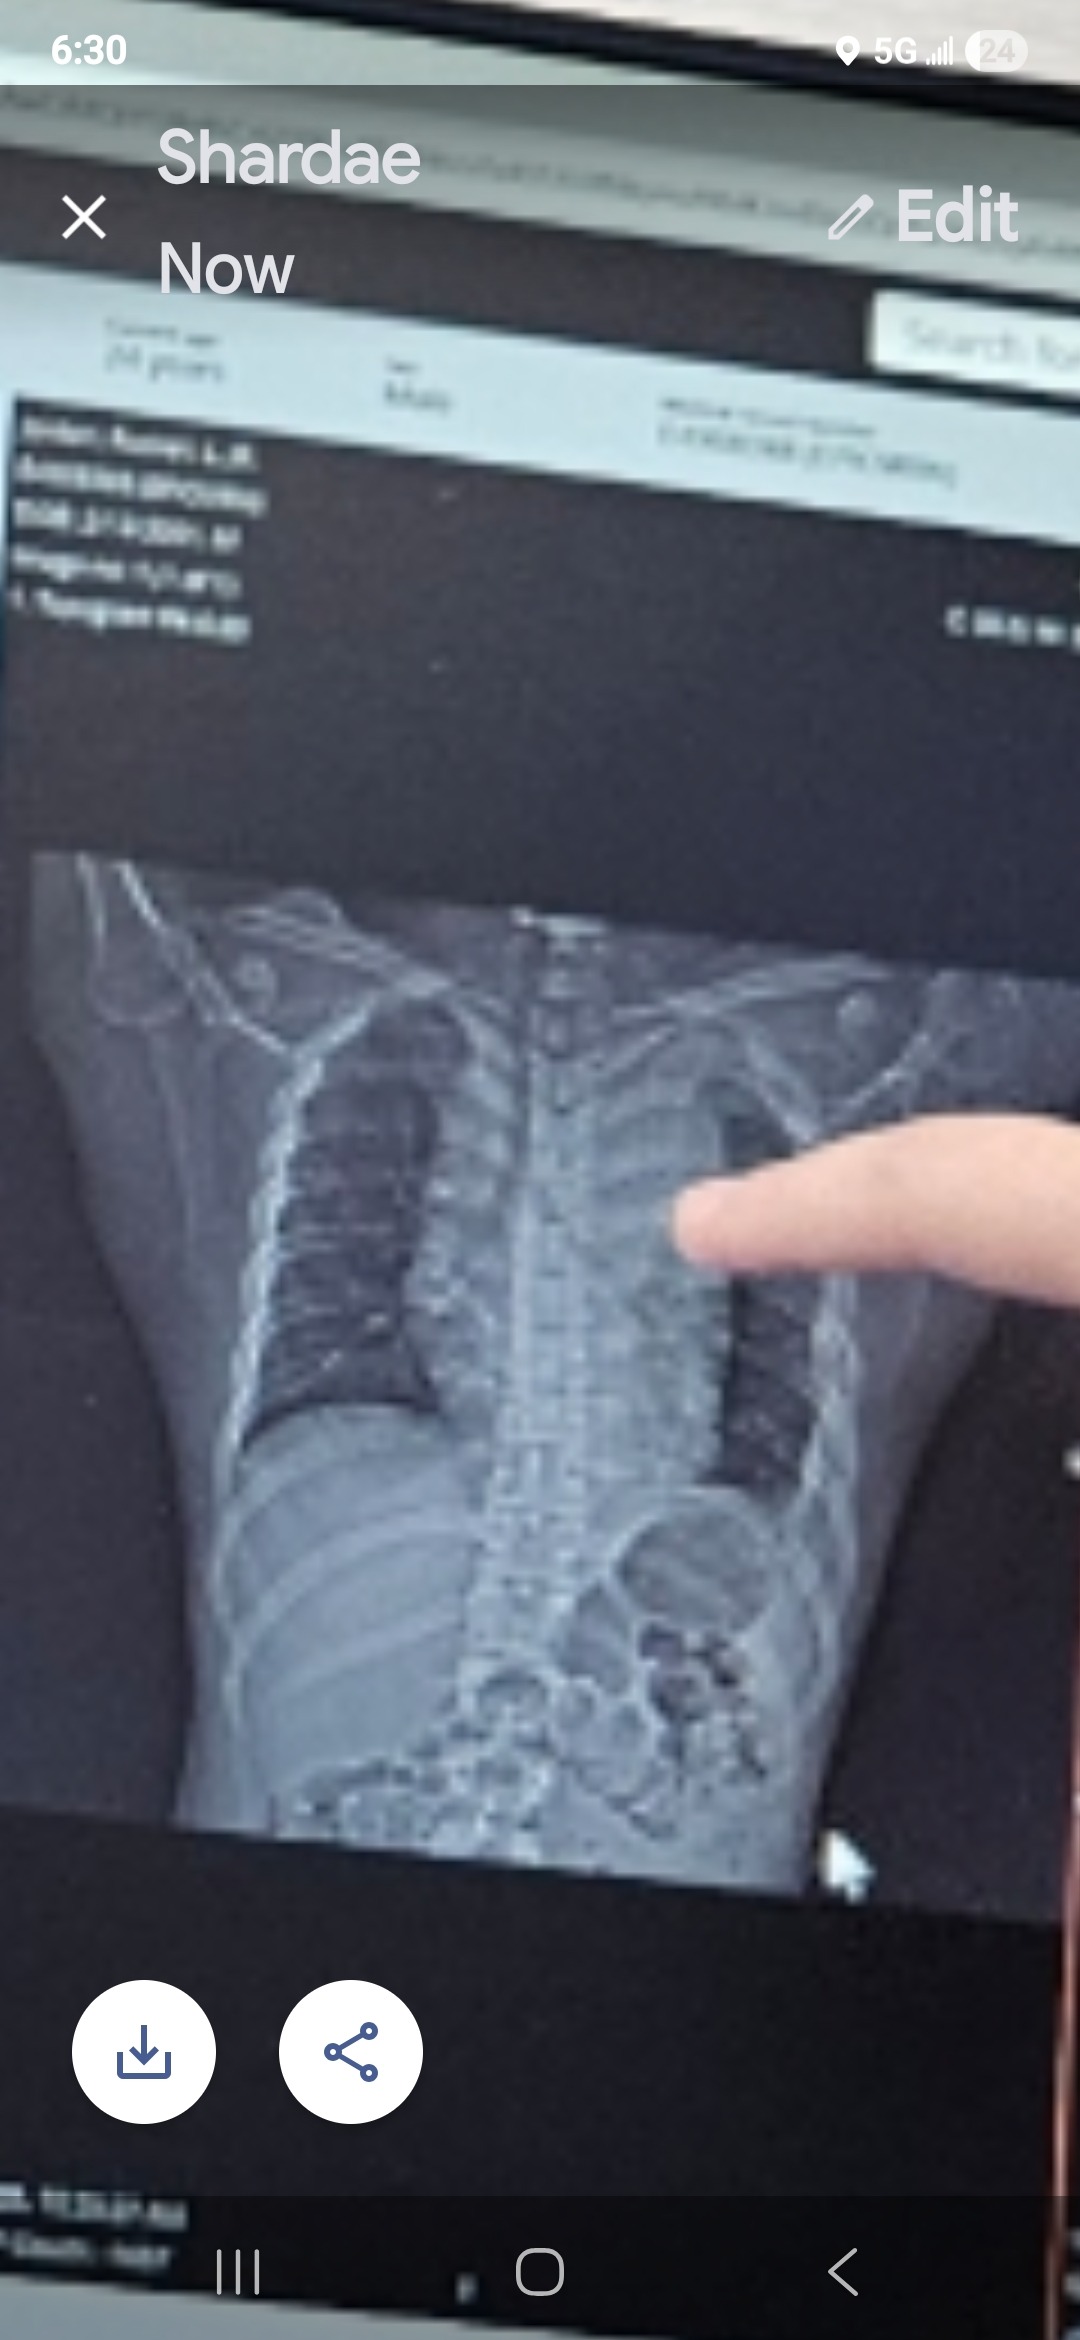

Recently, my brother started experiencing shortness of breath, chest pain, body aches, and neck pain. He went to the emergency room, which turned into a hospital admission. They found that he has a large mediastinal mass present (the size of a small football, it's 19 x 13 x 11). The mass is compressing his heart and trachea, causing deviation. His lungs are unable to fully expand. He had 800 ml of fluid removed from his left lung to assist breathing efforts. We are awaiting the pathology, but the doctors believe it's a lymphoma. They anticipate that he will start chemo after the pathology comes back confirming what they know: that he has cancer.